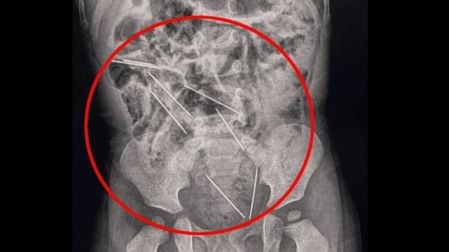

La mamá del pequeño se percató de lo ocurrido, por lo que de inmediato fue llevado al hospital en donde fue sometido a una exploración, en donde las radiografías mostraron que las agujas estaban dentro del sistema digestivo del niño.

Algunas de estas, se encontraban muy cerca de los órganos vitales del bebé, por lo que de inmediato los médicos lo sometieron a una cirugía de casi dos horas para retirar las agujas, y también recibió tratamiento por una pequeña lesión en el intestino delgado. Después de varios días en el hospital, se le dio de alta.